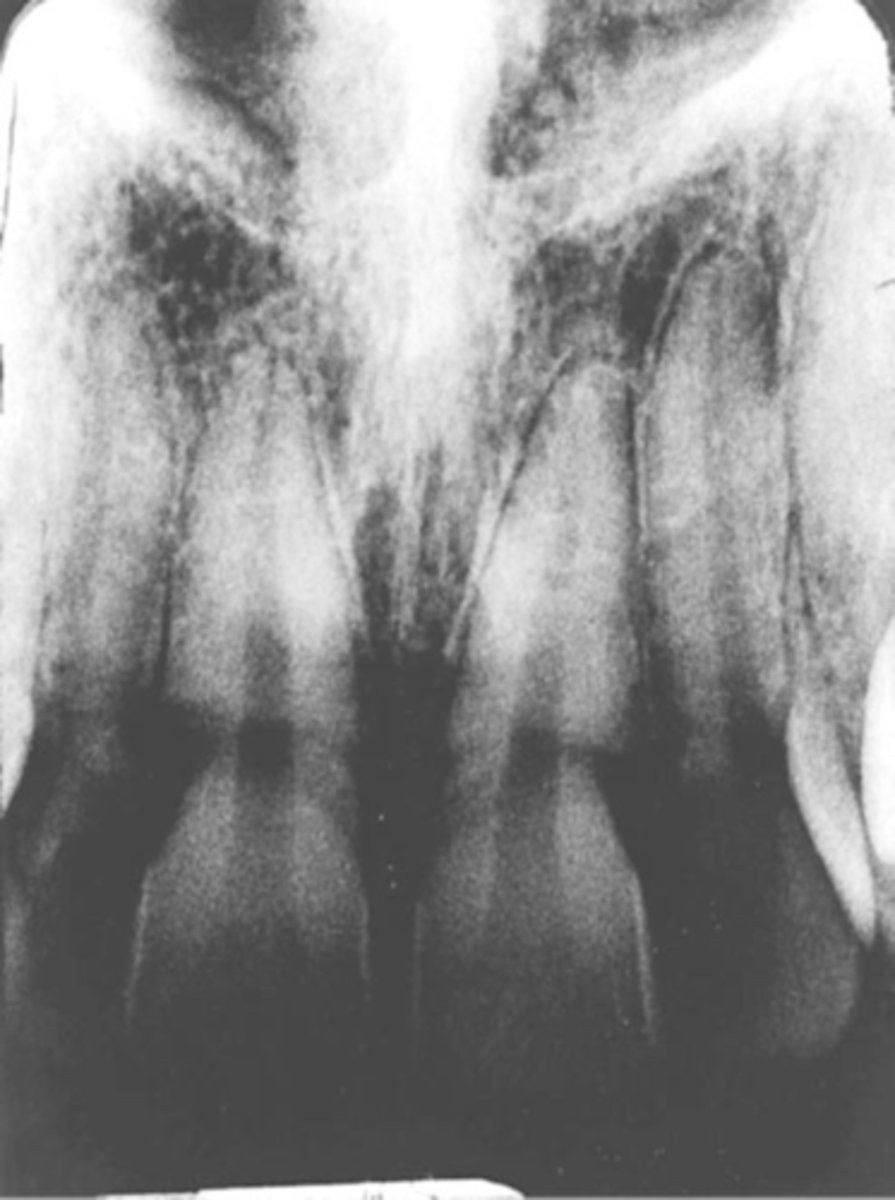

Double Exposure

-Double image is seen

-Same receptor was exposed twice in the patients mouth. This is a serious error and results in 2 retakes, one for each of the 2 areas previously radiographed

-To prevent always separate exposed and unexposed

Exposure-->Double Image/ Double Exposure

-Superimposed x-ray images

-Accidentally exposing film twice

-Maintain a systematic order to exposing radiographs